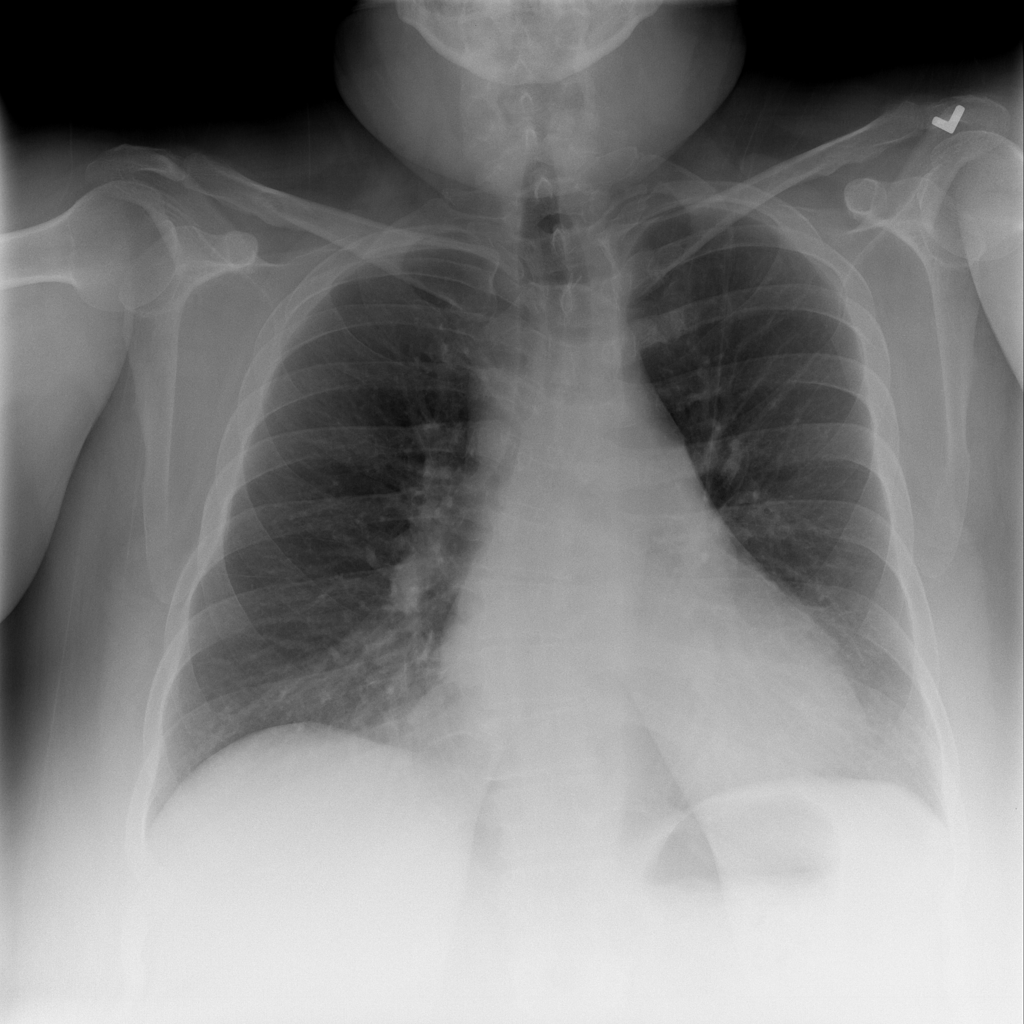

PAT-4639 · IMG-045Cardiomegaly

PAT-4639 · IMG-045

PA